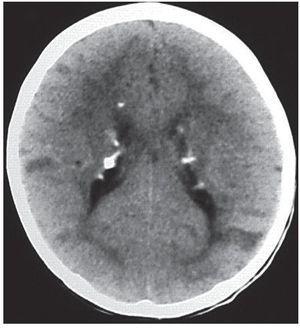

En la secuencia GRE los hamartomas subependimarios suelen identificarse como lesiones nodulillares hipointensas en las paredes de los ventrículos laterales, cuando estos están calcificados (fig. 9).

Figura 9. Secuencia eco de gradiente. Se constatan imágenes nodulillares hipointensas en la pared del ventrículo lateral derecho, correspondientes a hamartomas subependimarios calcificados (flechas).